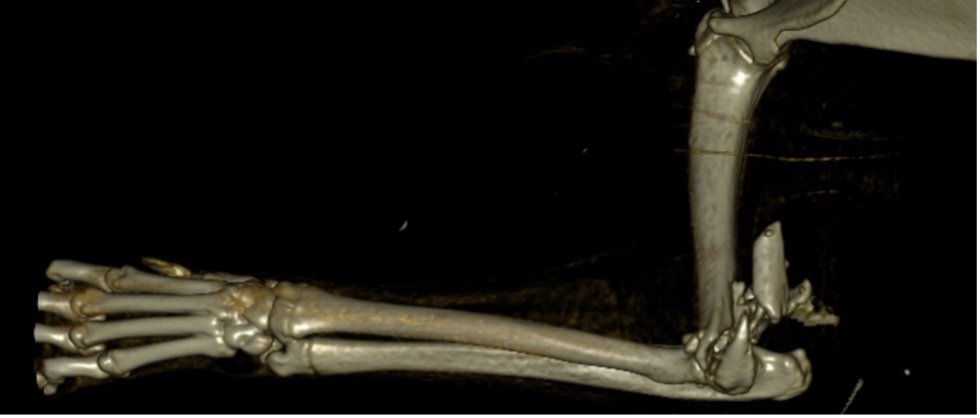

Exemple 1 :

Figure 1 : Pré-op